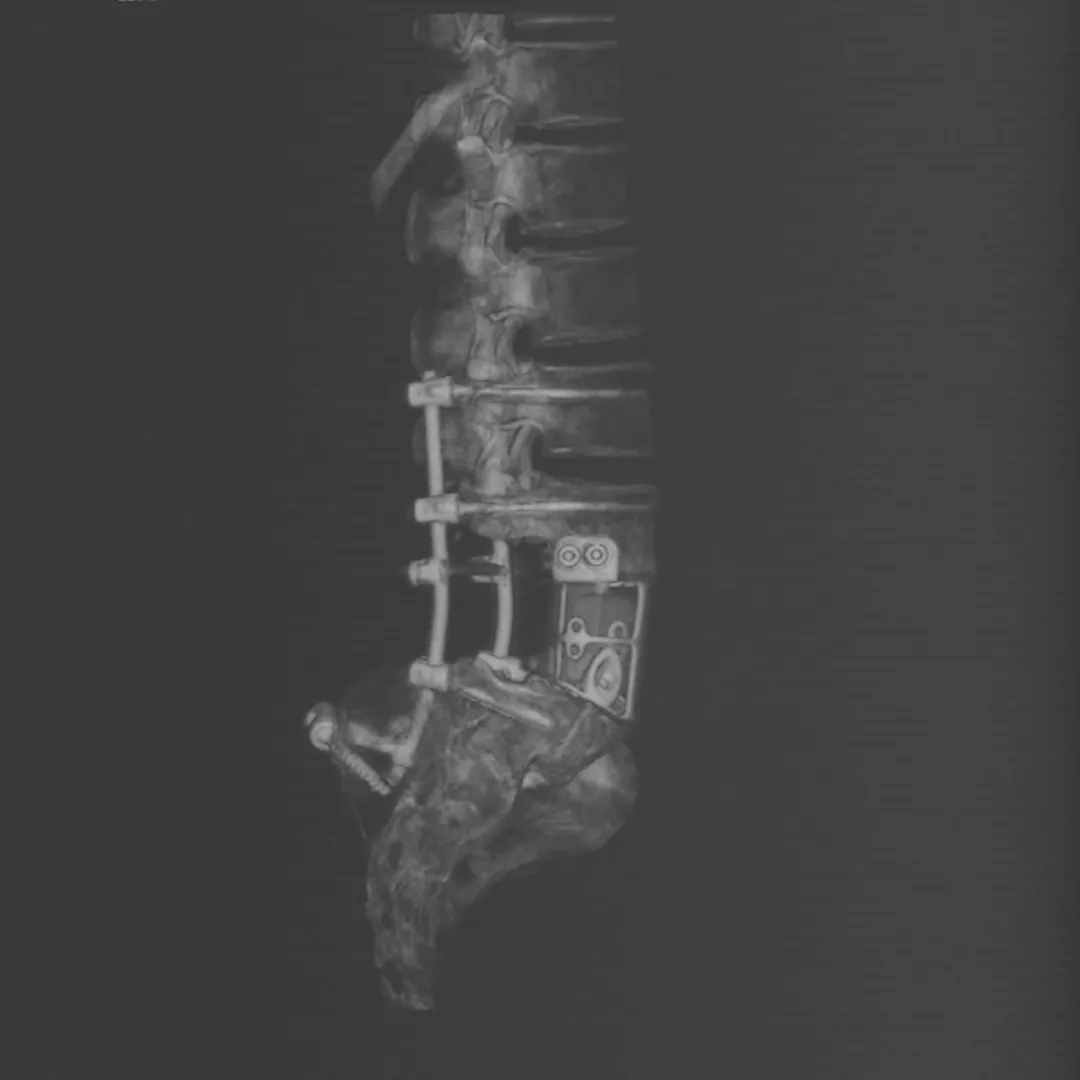

3D打印模型

经过周密的术前准备,郭征主任团队为患者实施了“前后路联合腰5肿瘤切除-3D打印定制式人工椎体重建内固定术”。经过术后康复,小贾已经顺利出院,在3D打印技术的加持下重新挺直腰杆,迈入光明的未来。

术后